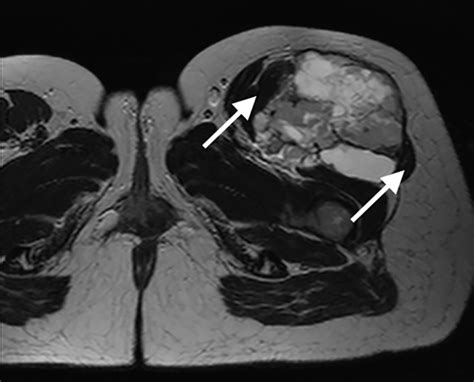

Once a doctor suspects a sarcoma, they will utilize a combination of diagnostic tools to confirm the diagnosis and determine the extent of the disease. The journey to a diagnosis usually involves imaging tests, such as X-rays, MRIs, or PET scans, which help identify the exact location and size of the tumor. A biopsy—where a small sample of the tissue is removed and examined under a microscope—is the gold standard for confirming exactly what is a sarcoma in a specific patient.

To truly grasp what is a sarcoma, one must look at the biological architecture of the human body. Sarcomas are malignant tumors that form in “soft” tissues or bone. Soft tissues include muscles, fat, blood vessels, nerves, tendons, and the linings of joints. Because these tissues provide structure and mobility, a tumor in these areas can often grow significantly before it is even detected, as it may push aside healthy tissue rather than immediately obstructing a vital organ.

One of the primary challenges in diagnosing a sarcoma is that early-stage symptoms are often non-specific. Many patients first notice a lump that may or may not be painful. Because these lumps are often mistaken for benign cysts or sports injuries, they can go undiagnosed for months. It is important to pay attention to persistent symptoms that do not resolve over time.